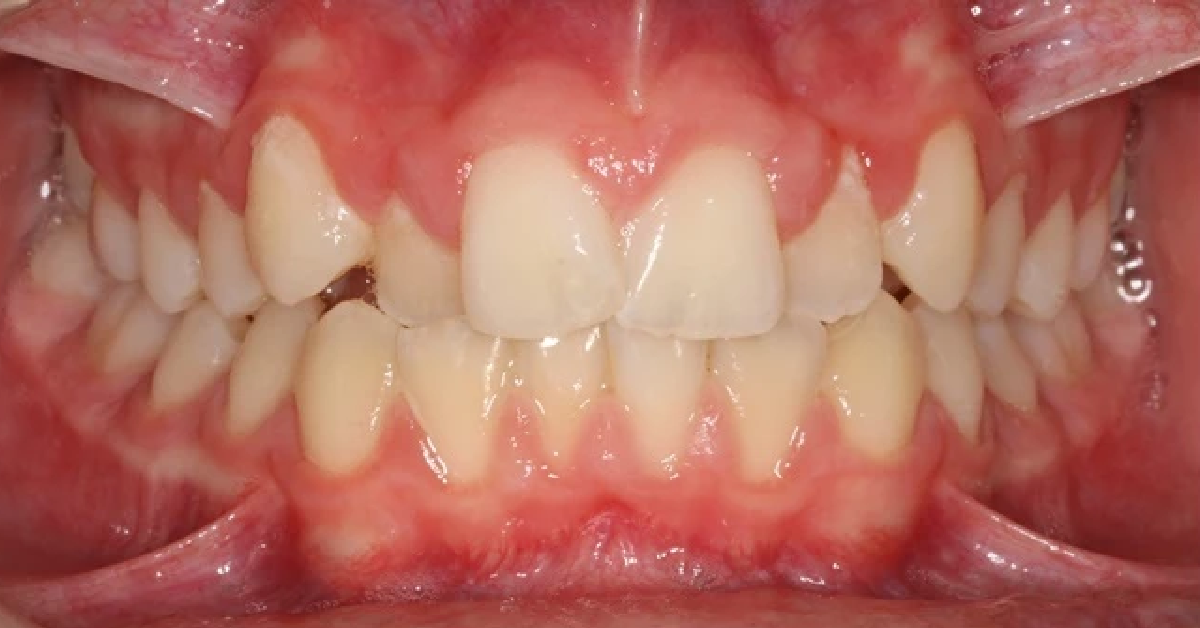

Vårt arbeid

Alle pasienter som vises har gitt skriftlig samtykke til at bildene kan brukes på klinikkens nettside.